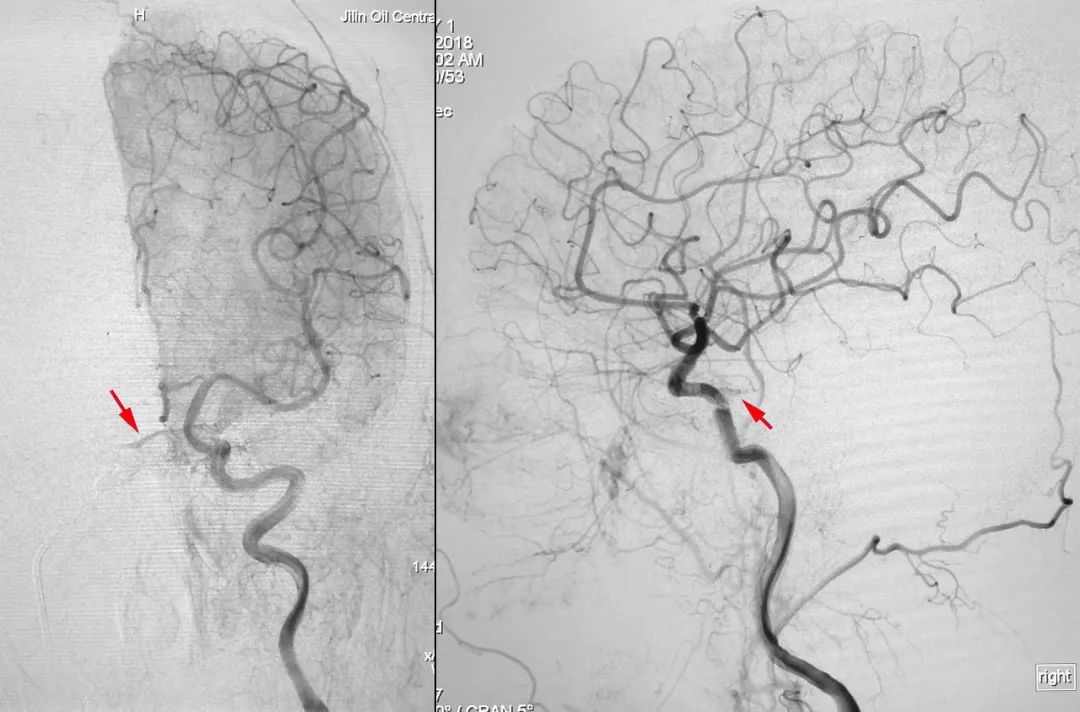

2018年10月12日行DSA示右侧海绵窦区硬脑膜动静脉瘘(Barrow D型),由双侧颈内、颈外动脉脑膜支供血,由右侧眼上静脉、岩下窦引流。

右侧颈总动脉正、侧位造影:

左侧颈总动脉正、侧位造影: